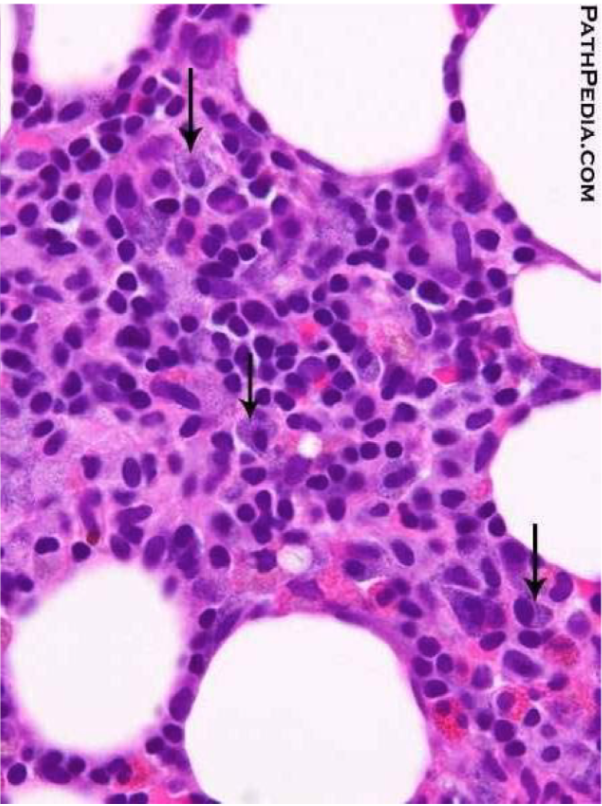

In dermatitis herpetiformis, _____ accumulate at _____

Fibrin and neutrophils accumulate at tips of dermal papillae

Fibrin and neutrophils accumulate at tips of dermal papillae —>

→ small microabscesses → subepidermal blisters

dermatitis herpetiformis